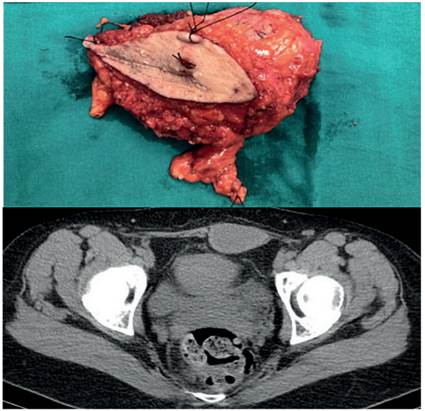

Las pacientes fueron mujeres jóvenes, con edades comprendidas entre los 22 y los 34 años (ME 29,6 años). La principal causa de consulta fue la aparición de una masa en la pared abdominal, localizadas sobre una cicatriz quirúrgica tipo Pfannenstiel, por cesárea en dos pacientes y por resección de un disgerminoma en la otra paciente, con dolor a la movilización. Sólo una de ellas consumía anticonceptivos orales. El diagnóstico se realizó mediante tomografía computarizada y biopsia con aguja gruesa guiada por ecografía (Tabla 1).

En todas las pacientes el tratamiento se realizó mediante una resección quirúrgica amplia con márgenes libres, que incluyó músculo y aponeurosis, respetando el peritoneo y la vascularización epigástrica. El defecto se reconstruyó con doble capa de malla de polipropileno en dos pacientes y en un caso con malla simple. Ninguna de las pacientes recibió tratamiento adyuvante.

Como se realizó en nuestras pacientes, el tratamiento de elección es la resección quirúrgica con márgenes libres, incluyendo la extirpación de las estructuras circundantes a la tumoración, para evitar las recidivas. No obstante, la cirugía presenta una alta tasa de recidiva, cercana al 25 %, llegando hasta el 60 % en algunas series. Debido al gran tamaño de las masas, la reparación primaria del defecto quirúrgico no suele ser posible, por lo que en muchos casos es necesario la realización de colgajos o la utilización de material protésico o mallas 9.